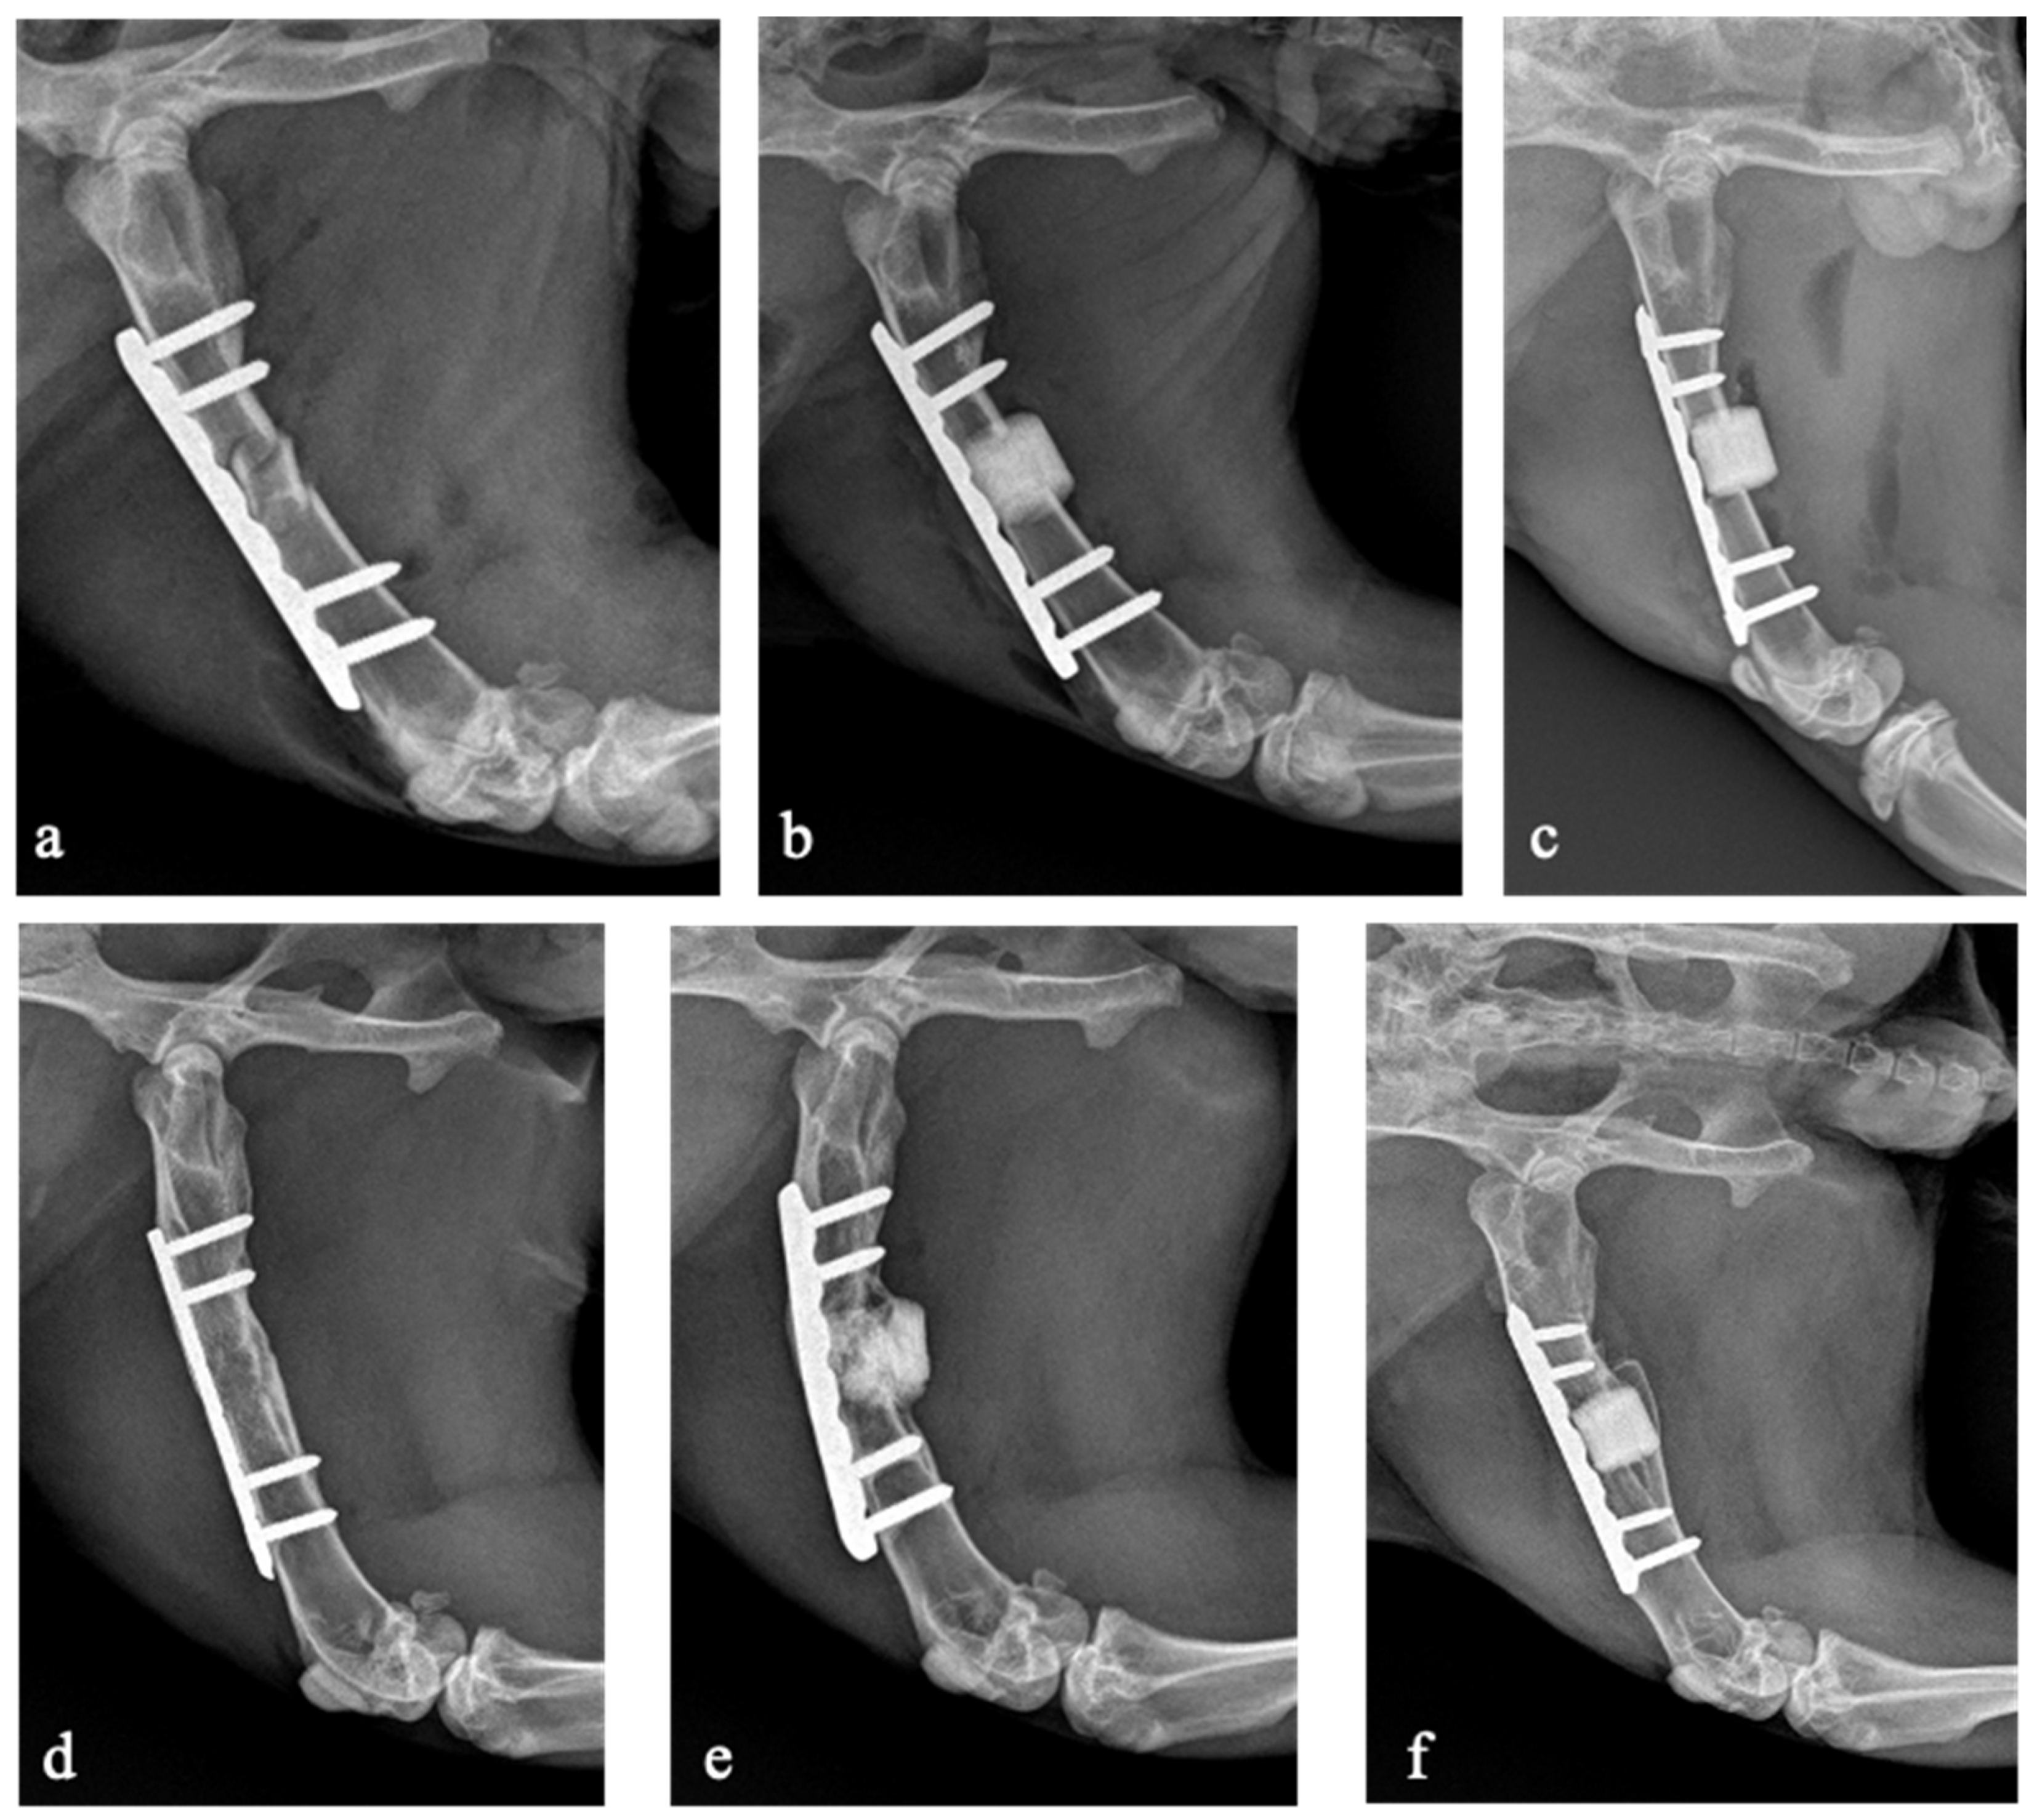

3.1. Mechanical Complications

3.2. Bone Union

- Vandenbulcke, F.; Anzillotti, G.; Ravasio, G.; Malagoli, E.; Conte, P.; Balzarini, B.; Kirienko, A.; Kon, E. External fixator-assisted plating osteosynthesis in a rabbit model of femoral bone defects appears to be a feasible and reproducible surgical technique: Preliminary insights from a bone substitute study. J. Exp. Orthop. 2023, 10, 77. [Google Scholar] [CrossRef] [PubMed]